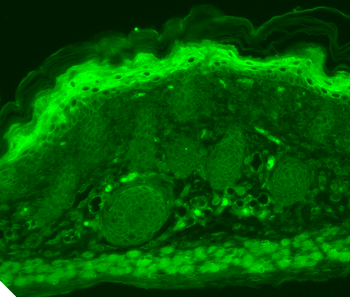

Immunohistochemical staining of human colon cancer using TRPV1 antibody